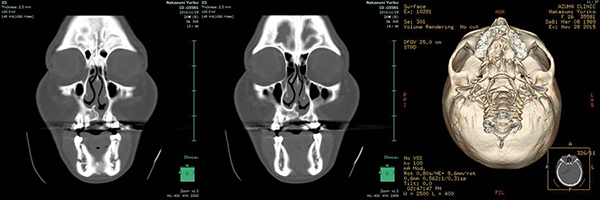

| 診断名 | 他院での矯正治療の既往がある左側唇顎口蓋裂に起因する顔面非対称を伴う 骨格性下顎前突 |

| 顎矯正手術術式 | 上顎骨前方移動+cant修正術(Le Fort Ⅰ型骨切り術) 下顎骨後方移動術(両側下顎枝矢状分割術) |

| 顎矯正手術時年齢 | 28才2か月 |